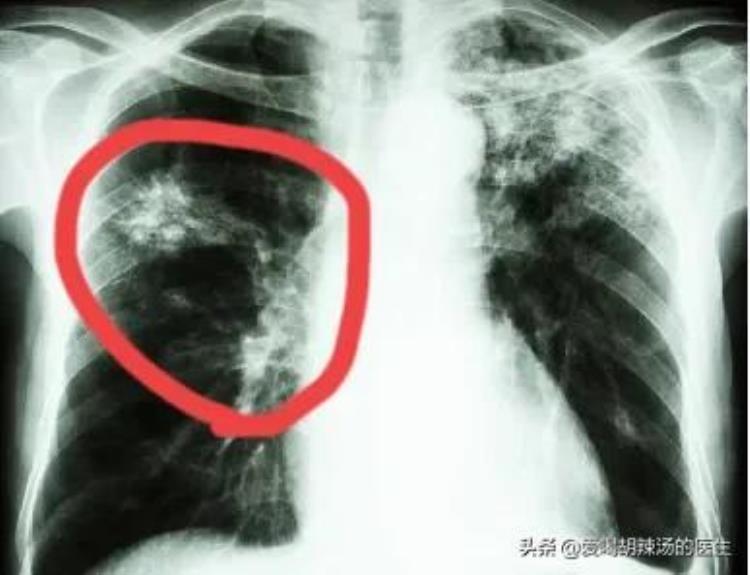

肺结核的原发综合征

二、肺结核的分类:1.原发性肺结核:原发综合征(原发灶、肺门淋巴结结核、淋巴管炎)

①浸润性肺结核:小斑片影、肺尖空洞(最常见)

②空洞性肺结核:空洞形态不一、虫蚀样空洞薄壁空洞

③纤维空洞性肺结核:厚壁空洞

④结核球:卫星灶

⑤干酪性肺炎:大叶肺炎磨玻璃影、虫蚀空洞。

原发性与继发性肺结核的鉴别点